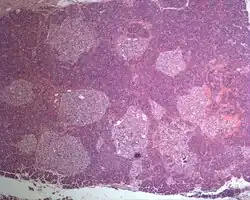

| Photographic image of the numerous islets of various sizes in the pancreas of a patient with Mahvash disease | |

Most patients with Mahvash disease are diagnosed in adulthood. Patients with Mahvash disease usually present with vague abdominal discomfort. Imaging with CT or MRI identifies a very large pancreas with one or more tumors. Biochemical testing shows marked hyperglucagonemia (hundreds-fold elevated). If the tumors are resected, they are found to be neuroendocrine tumors that usually express glucagon. In the tumor margin, pancreatic alpha cell hyperplasia is pervasive, numerous large islets composed of mostly alpha cells are evident, and multiple microadenomas and small neuroendocrine tumors often are present. The pancreatic neuroendocrine tumors are the main health concern for patients with Mahvash disease. Although the tumors commonly are indolent, death due to liver metastasis has been reported.[3] In patients with complete loss of glucagon receptor function, Mahvash disease can present at younger age with portal hypertension and hepatic encephalopathy.[11]